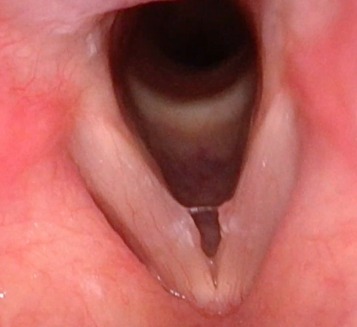

Ses Kısıklığı Kanser Belirtisi midir? Ses kısıklığı, hemen herkesin hayatında en az bir kez yaşadığı yaygın bir şikâyettir. Çoğu zaman basit ve geçici nedenlere bağlıdır. Ancak uzun süre devam eden, nedeni açıklanamayan ses kısıklığı, bazı ciddi hastalıkların, özellikle de kanserin erken belirtisi olabilir. Bu nedenle ses kısıklığı hafife alınmamalıdır. Ses Kısıklığı Nedir? Ses kısıklığı; sesin normal tonunun değişmesi, boğuklaşması, çatallanması ya da daha zor çıkması durumudur. Bu sorun genellikle ses tellerinin sağlıklı titreşememesi sonucu ortaya çıkar. Ses Kısıklığının En Sık Nedenleri Ses kısıklığının büyük çoğunluğu kanser dışı nedenlere bağlıdır: Bu durumlarda ses kısıklığı genellikle 1–2 hafta içinde kendiliğinden düzelir. Ses Kısıklığı Ne Zaman Kanser Belirtisi Olabilir? Ses kısıklığı her zaman kanser anlamına gelmez. Ancak aşağıdaki durumlarda mutlaka dikkatli olunmalıdır: Bu belirtiler özellikle gırtlak (larinks) kanseri açısından uyarıcı olabilir. Kimler Daha Fazla Risk Altındadır? Aşağıdaki kişilerde ses kısıklığı daha ciddiye alınmalıdır: Ses Kısıklığında Ne Zaman Doktora Gidilmeli? Aşağıdaki durumlarda Kulak Burun Boğaz (KBB) hekimine başvurulmalıdır: Erken tanı, özellikle kanser şüphesinde hayat kurtarıcıdır. Sonuç Ses kısıklığı çoğu zaman masum nedenlere bağlıdır. Ancak uzun süren, açıklanamayan ve giderek artan ses kısıklığı mutlaka ciddiye alınmalı ve uzman hekim tarafından değerlendirilmelidir. Erken dönemde yapılan muayene, hem basit ses teli sorunlarının hem de olası ciddi hastalıkların zamanında teşhis edilmesini sağlar. Sesiniz sağlığınızın aynasıdır.İhmal etmeyin, geçmeyen ses kısıklığını mutlaka kontrol ettirin.

Ses kısıklığı, ses tellerinin düzgün titreşememesi sonucu oluşan, çoğu zaman geçici ancak bazen ciddi hastalıkların da belirtisi olabilen yaygın bir şikâyettir. Özellikle uzun süren (2 haftadan fazla devam eden) ses kısıklıkları mutlaka bir KBB doktoru tarafından değerlendirilmelidir. Ses Kısıklığının En Yaygın Nedenleri 1. Üst Solunum Yolu Enfeksiyonları Grip, soğuk algınlığı ve larenjit gibi enfeksiyonlarda ses telleri şişer ve ses kısıklığı ortaya çıkar.Belirtiler: Boğazda yanma, ağrı, öksürük, sesin çatallanması. 2. Aşırı Ses Kullanımı Öğretmenler, çağrı merkezi çalışanları, şarkıcılar ve gün içinde çok konuşan kişilerde sık görülür.Sürekli bağırmak, yüksek sesle konuşmak veya yanlış ses tekniği kullanmak ses tellerini zorlar. 3. Reflü (Laringofarengeal Reflü) Mide asidinin ses tellerine ulaşması ses kısıklığının sık görülen nedenlerindendir.Belirtileri: Sabah ses kısıklığı, boğazda gıcık hissi, sık boğaz temizleme ihtiyacı. 4. Alerjiler Alerjik reaksiyonlar ses tellerinde ödem oluşturabilir.Polen, toz veya kimyasal kokulara duyarlılığı olan kişilerde daha sık görülür. 5. Sigara ve Zararlı Kimyasallar Sigara içmek ses tellerini tahriş eder, uzun vadede kalıcı hasarlara ve ciddi hastalıklara yol açabilir.Ayrıca dumanlı, tozlu veya kimyasallarla dolu ortamlarda çalışmak risk artırır. 6. Ses Teli Nodülleri ve Polipleri Ses tellerinin fazla zorlanması sonucu oluşan iyi huylu oluşumlardır.Özellikle uzun süre geçmeyen kısıklıklarda nodül olasılığı yüksektir. 7. Tiroid Problemleri Tiroid bezinin az çalışması sesin kalitesini etkileyebilir.Kısık, yorgun ses ve boğazda baskı hissi görülebilir. 8. Nörolojik Problemler Çok nadir olsa da sinir sistemi kaynaklı rahatsızlıklar ses tellerinin hareketini etkileyebilir. Ses Kısıklığı Nasıl Geçer? 1. Sesin Dinlendirilmesi Bağırmaktan, yüksek sesle konuşmaktan ve fısıltı yapmaktan kaçınmak gerekir.Fısıltı, ses tellerine normal konuşmadan daha çok yük bindirir. 2. Bol Su İçmek Ses tellerinin nemli olması iyileşmeyi hızlandırır. Günde en az 1,5–2 litre su önerilir. 3. Buhar ve Nemlendirme Sıcak duş buharı veya odada nemlendirici cihaz kullanmak ses tellerinin rahatlamasına yardımcı olur. 4. Reflü Tedavisi Reflüye bağlı ses kısıklığında: 5. Alerji Kontrolü Alerjenlerden uzak durmak ve uygun antihistaminik tedavi sesin düzelmesini sağlar. 6. Sigaranın Bırakılması Ses tellerinin iyileşmesi için en önemli adımlardan biridir. 7. KBB Muayenesi ve Gerekirse Endoskopi 2 haftadan uzun süren ses kısıklığında KBB muayenesi şarttır.Endoskopik muayene ile ses telleri doğrudan görüntülenir ve nodül, polip, enfeksiyon gibi durumlar netleşir. Ne Zaman Doktora Başvurmalısınız? Sonuç Ses kısıklığı çoğu zaman basit nedenlerle gelişse de, uzun süre devam eden şikâyetlerde altta yatan ciddi bir problem olabilir. Erken teşhis, hem ses kalitesini korur hem de olası hastalıkların ilerlemesini engeller.

Kulak Burun Boğaz (KBB) muayenesi, kulak, burun, boğaz ve baş-boyun bölgesiyle ilgili sağlık sorunlarının değerlendirilmesi için yapılan kapsamlı bir incelemedir. Bu muayene sayesinde; işitme kaybı, burun tıkanıklığı, geniz akıntısı, ses kısıklığı, boğaz ağrısı, sinüzit veya baş dönmesi gibi birçok problem doğru şekilde teşhis edilir. 🔍 KBB Muayenesi Neden Yapılır? KBB muayenesi; hem rutin kontrollerde hem de hastanın belirli bir şikâyetle başvurması durumunda yapılır.En sık muayene sebepleri şunlardır: Bu şikâyetler, yaşam kalitesini önemli ölçüde etkileyebileceğinden erken tanı büyük önem taşır. 🩹 KBB Muayenesi Nasıl Yapılır? KBB muayenesi genellikle üç temel bölgeyi kapsar: kulak, burun ve boğaz. 👂 Kulak Muayenesi Uzman hekim, otoskop adı verilen özel bir cihazla dış kulak yolunu ve kulak zarını inceler. Gerekli durumlarda işitme testi (odyometri) uygulanarak kulaktaki ses algılama düzeyi değerlendirilir. 👃 Burun Muayenesi Burun içi ve sinüs kanalları endoskopik kamera yardımıyla detaylı şekilde incelenir. Bazı durumlarda sinüs filmi veya tomografi ile detaylı görüntüleme gerekebilir. 👄 Boğaz Muayenesi Ağız, bademcikler, gırtlak ve ses telleri endoskop veya laryngoskop ile kontrol edilir. ⚕️ KBB Muayenesi Ne Kadar Sürer? Genellikle 10–20 dakika arasında tamamlanır.Eğer ileri tetkik veya endoskopik inceleme gerekiyorsa süre uzayabilir.Muayene tamamen ağrısızdır ve hastalar aynı gün günlük yaşamlarına dönebilir. 💡 KBB Muayenesi Öncesinde Dikkat Edilmesi Gerekenler 🌿 Sonuç KBB muayenesi; kulak, burun, boğaz ve solunum yolları ile ilgili hastalıkların erken teşhisi için büyük önem taşır.Düzenli kontroller sayesinde hem kronik sorunlar önlenebilir hem de yaşam kalitesi artırılabilir. Prof. Dr. Ahmet Özdoğan📍 Abide-i Hürriyet Cd No:147, Şişli / İstanbul📞 0 (542) 450 85 30🌐 profdrhasanahmetozdogan.com